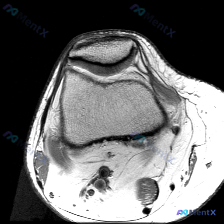

刚整理了一个很有代表性的读片病例,临床怀疑膝关节软骨异常,只提供了一张膝关节MRI轴位T1加权图像,分享一下完整分析思路,大家一起讨论。

本次仅提供单张膝关节MRI轴位T1加权图像,影像学观察结果如下:

- 骨骼结构:髌骨、股骨髁骨皮质连续,未见明显骨折线,骨髓信号符合正常T1加权表现

- 髌股关节:髌骨关节软骨、股骨滑车软骨表面光滑,信号均匀,未见明确局灶性缺损或变薄,髌股关节对合关系良好,无脱位/半脱位

- 软组织结构:内外侧支持带结构正常,无明显信号中断;未见显著异常关节积液;髌下脂肪垫无明显信号异常;腘窝血管结构可见,无异常肿块;髌骨及股骨滑车边缘无明显骨赘增生,关节间隙宽度正常